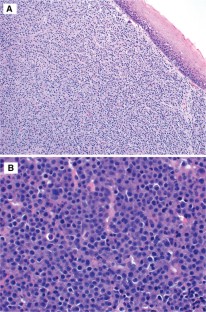

Fig. 2